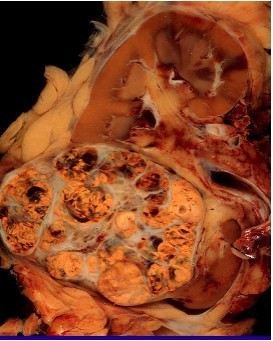

Conventional (clear cell) Renal cell carcinoma

FIRST AID:

- Origin= PCT cells–> polygonal clear cells filled with accumulated lipids, carbs

Presentation:

- Male, 50-70 years

- Smoker, obese

- Hematuria, palpable mass

- Secondary polycythemia, flank pain, fever, weight loss

- Invades renal vein–> IVC–> hematogenous spread–> mets to bone, lung

* MOST common renal malignancy

• Hereditary cases, like Von Hippel- Lindau (VHL) chromosome 3 (3p) VHL tumor suppressor gene

- Cause paraneoplasic syndrome: ectopic EPO–> polycythemia, ACTH–> cortisol, PTHrP–> hypercalcemia, bone loss

- Silent in retroperitoneum (presents at metastatic stage)

Treatment: resection (if localized), resistant to chemo, radiation

Presentation: – Hematuria

– Few with the classic triad of hematuria, flank pain, and a palpable mass

– Metastasis

– Paraneoplastic syndrome: Hypercalcemia, hypertension, polycythemia (produces EPO)

– Incidental finding (CT or MRI) Risk factor is tobacco smoking

Grossly: Clear cell RCC: well circumscribed, golden yellow, cystic solid, hemorrhagic, necrosis.